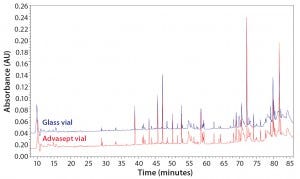

Figure 12: Magnified ultraperformance liquid chromatography with ultraviolet detection (UPLC-UV) chromatograms of trypsin-digested antibody rightway in a glass vial (bottom trace) and an Advasept vial (top trace)

Figure 13: Magnified UPLC/UV chromatograms of ASP-N digested antibody rightway in a glass vial (bottom trace) and an Advasept vial (top trace)

Table 4: Percent modification — methionine oxidation and deamidation

As Figures 12 and 13 illustrate, both glass and Advasept vial samples showed no major difference in UPLC/UV chromatograms from both trypsin and AspN digestion, with 100% sequence coverage by MS detection. Deamidation levels observed with MS are comparable for both glass and Advasept vials (Table 4). We saw higher oxidation levels in glass vials than in Advasept vials, which could be attributed to surface interaction between MAbs and the glass surface causing more oxidation than in plastic Advasept vials.